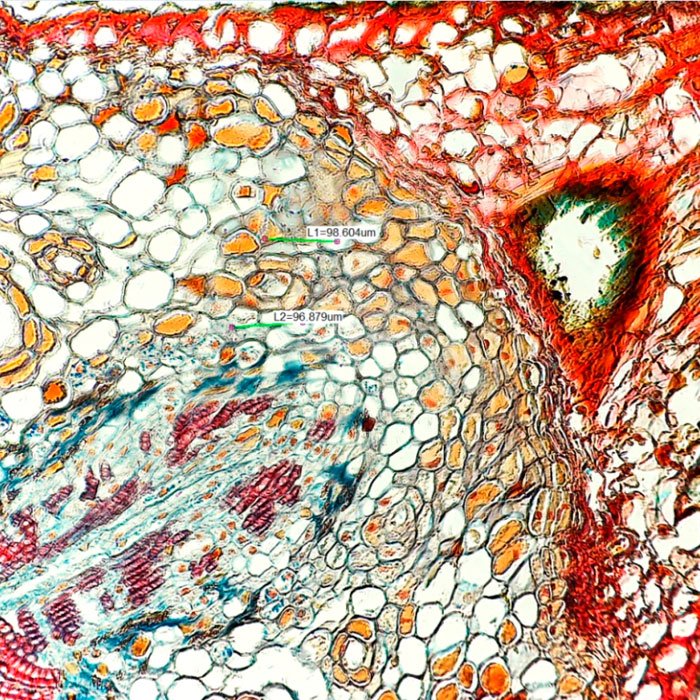

Цифровой видеоокуляр «Миктрон» 5 Мп: переход от наблюдения к цифровому анализу

Модернизируйте ваш микроскоп с помощью цифрового видеоокуляра «Миктрон». Это устройство превращает стандартный оптический микроскоп в мощную цифровую станцию для захвата изображений и видео. Идеальное решение для образовательных учреждений, лабораторий, производственного контроля и любителей науки.

Видеоокуляр «Миктрон» — это не просто камера, а полноценный инструмент для документирования исследований, проведения измерений и демонстрации микромира на экране компьютера или проектора.

- Высокое разрешение 5 Мп: Достаточно для детализированной съемки большинства биологических, металлографических и других образцов.

- Захват статичных изображений и запись видео с возможностью настройки параметров (разрешение, частота кадров, баланс белого, экспозиция).

- Измерения: Линейные размеры, углы, площади, периметры объектов на изображении после калибровки по шкале микроскопа.

- Обработка изображений: Коррекция яркости, контрастности, наложение масштабной линейки, текстовых аннотаций.

- Режим живого изображения (Live View): Просмотр происходящего в микроскопе в реальном времени на мониторе.

Цифровой видеоокуляр «Миктрон» находит применение в различных сферах, где требуется визуальный анализ и фиксация результатов.

- Наука и исследования: В биологических, медицинских, материаловедческих лабораториях для документирования экспериментов.